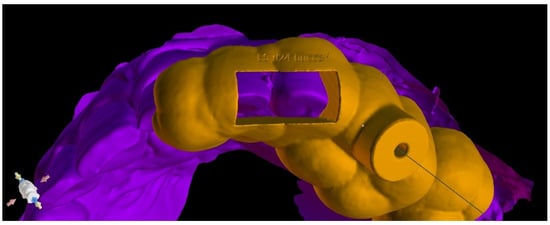

After the implant position was accepted by a clinician, an endodontic guide (teeth-supported) was designed for a sleeveless, static navigation of the image obtained from an intraoral scan (Figure 12). The guide covered the labial and palatal surfaces of the adjacent teeth (13-23) to obtain adequate intraoral stabilization. The use of stabilizing pins is unnecessary in such cases. The guide tube was designed so that the top of the sleeve was 21 mm from the radiographically visible root canal lumen. The guide sleeve was 6 mm long and 1.5 mm in diameter. The endodontic guide was printed on a resin 3D printer (Phrozen Sonic Mini 4K) using a transparent resin designed for printing surgical guides (NextDent SG)—a class IIa product that can be used in the oral cavity (Figure 13). Post-processing was conducted in accordance with the resin manufacturer’s instructions to avoid dimensional changes [24]. A master model was printed to check the accuracy of the guide’s fitting (Figure 14).

Figure 13. Three-dimensional printed endodontic guide.